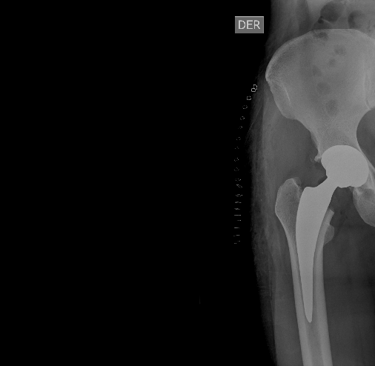

El reemplazo de cadera es una cirugía en la que se retira la articulación de la cadera dañada y se reemplaza por una prótesis artificial (Metal).

Esta intervención es indicada principalmente para pacientes que sufren de artrosis severa o lesiones en la cadera que causan un dolor intenso y limitación en la movilidad.